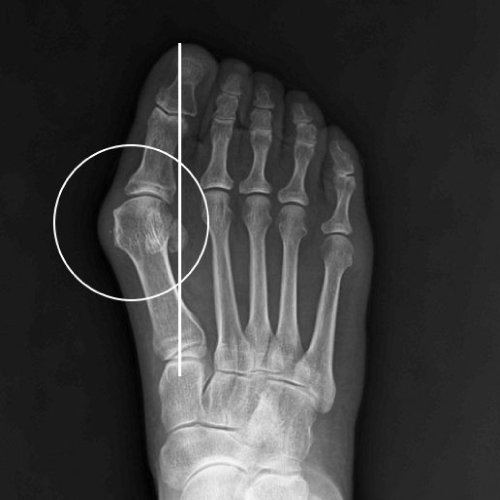

무지외반증 수술 전

2020.12.10

무지외반증 수술 후

2021.01.18

ㆍ환자 동의를 받은 자료이며, 이미지 사진은 실물과 다를 수 있습니다.

ㆍ모든 자료는 새움병원 자료입니다.